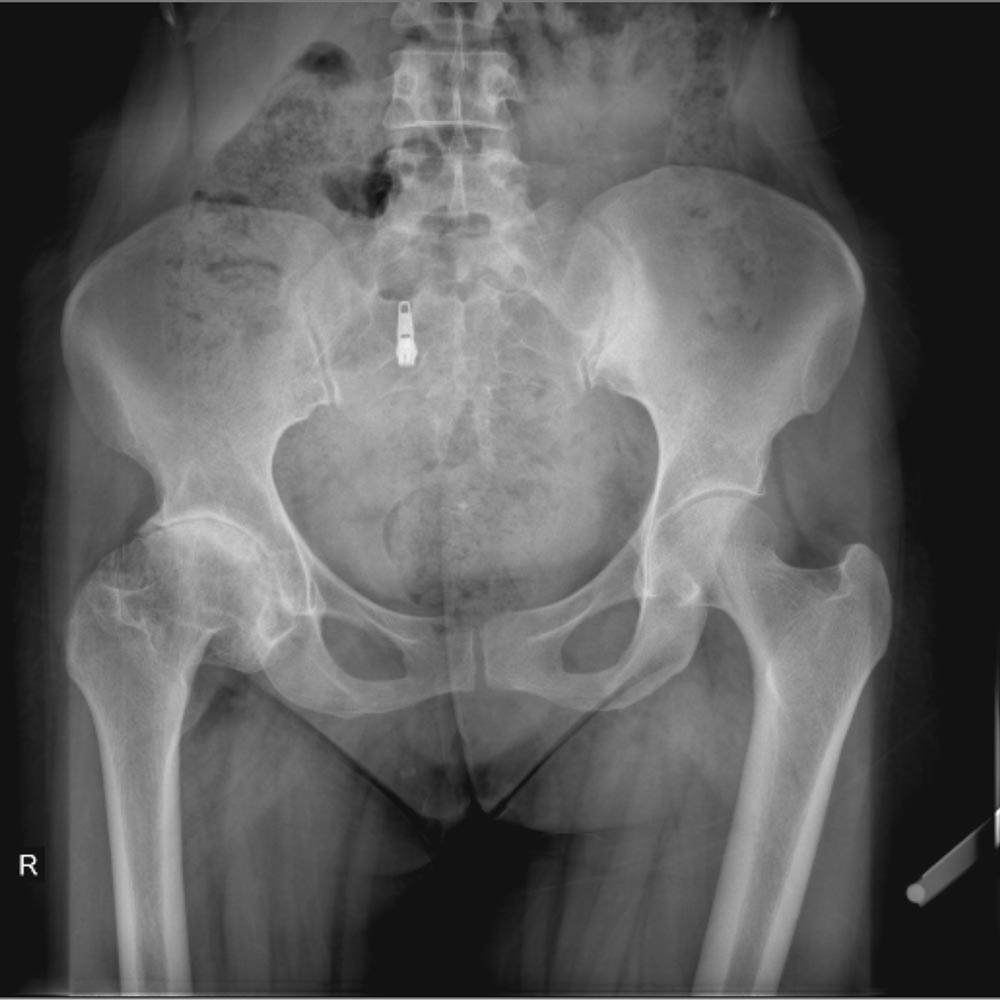

در نهایت، روش های تصویر برداری مثل رادیوگرافی به تشخیص بیماری کمک میکند. مهمترین روش تصویربرداری برای تشخیص ساییدگی لگن رادیوگرافی ساده است. تشخیص این بیماری نیاز به سی تی اسکن یا ام ار آی ندارد.

در تصویر رادیوگرافی از مفصل، چون غضروف نازک شده است فاصله مفصلی یا فاصله بین دو استخوانی که مفصل را تشکیل داده اند و در حد چند میلیمتر است کاهش پیدا میکند و در کناره های استخوان های تشکیل دهنده مفصل استخوان اضافی دیده میشود.

همچنین ممکن است کیست های استخوانی در بالای استابولوم یا در سر استخوان ران دیده شود.

در زیر تصاویری از عکس ساییدگی لگن در چند بیمار را میبینید. با کلیک بر روی هر کدام تصویر بزرگتری از آن را خواهید دید.